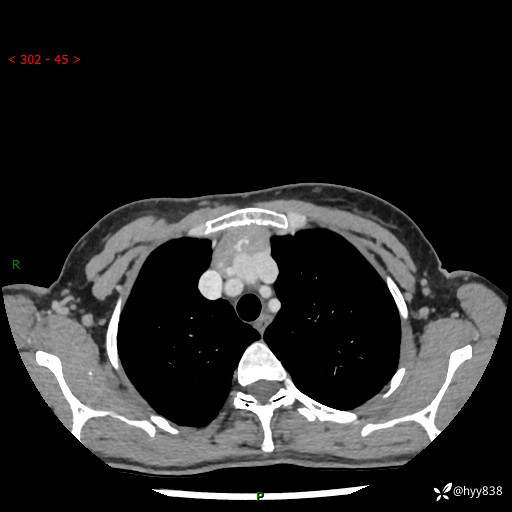

增强动脉期+静脉期